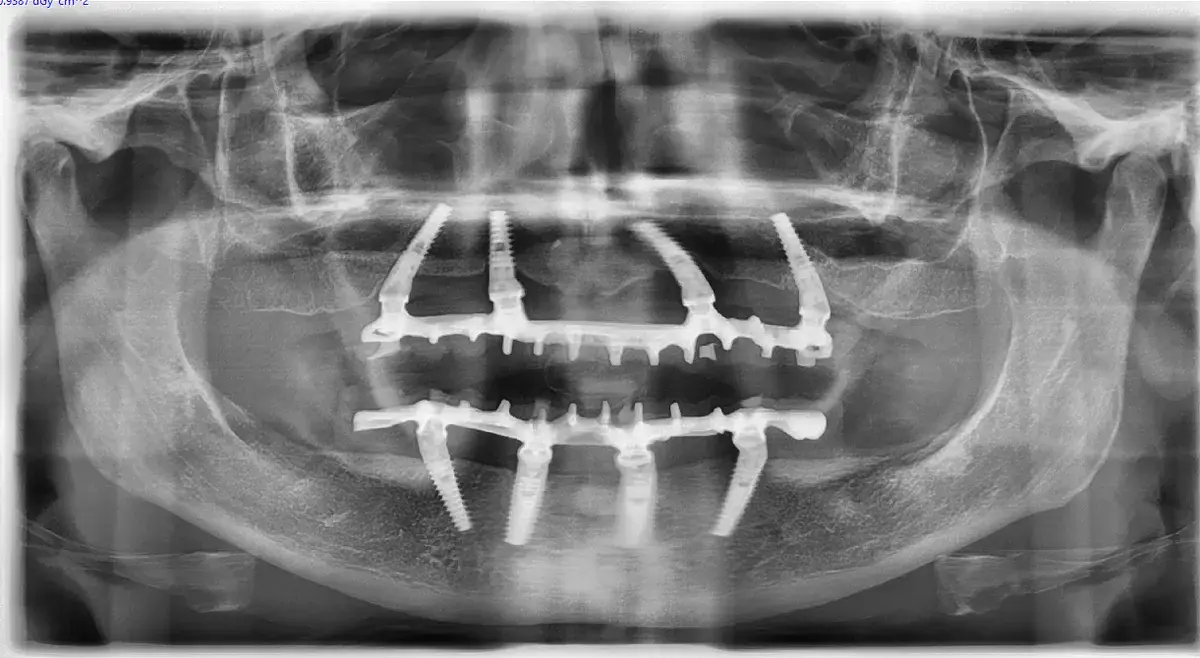

In chirurgia implantare, ogni decisione intraoperatoria ha un impatto diretto sulla vascolarizzazione del sito. Non si vede a occhio nudo, ma si misura nei risultati a distanza.

Lo scollamento del lembo, la sequenza di fresatura, il torque di inserimento, la temperatura generata — sono tutte variabili che determinano quanta rete vascolare sopravvive attorno all’impianto. E la rete vascolare è ciò che decide se l’osso si rigenera o si riassorbe.